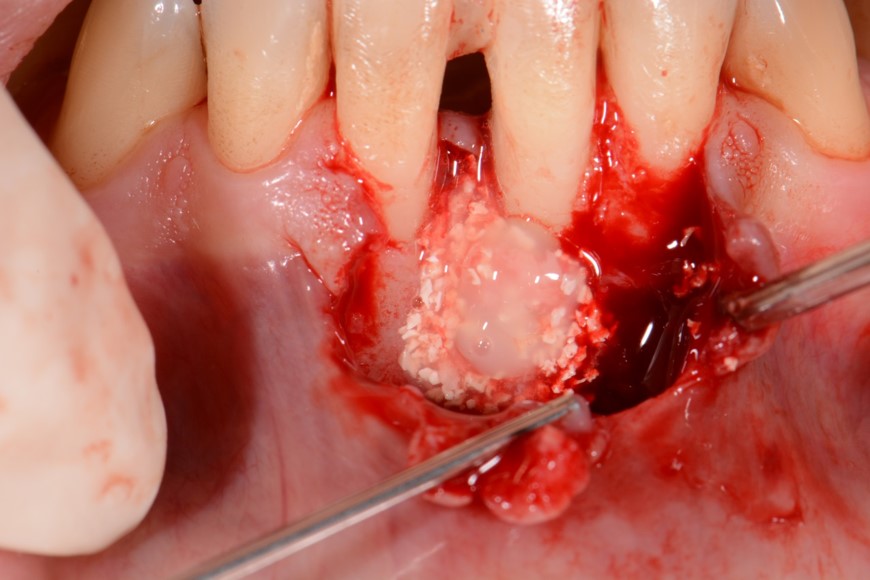

05/12 - Application of small cerabone® granules mixed with Straumann® Emdogain®.Two-wall intrabony defect treated using cerabone® and Straumann® Emdogain® - Dr. D. Rakasevic & Prof. Dr. S. Jankovic